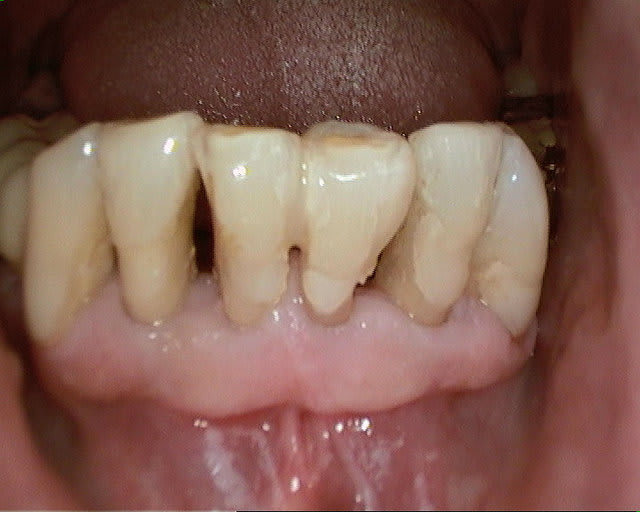

un cas récent os vestibulaire très fin.

Serrage manuel, sans lambeau. Extraction implantation immédiate

le 4.5*11 me semblait convenable. J'avais peur que si je metais du 4*11 l'espace entre les cretes vestibulaires et l'implant allait creer une recession si je ne comblait pas ce vide

Rappelons qu'en mesurant j'ai 1.25 mm d'os au final et pas 0.5-0.8mm